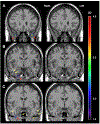

Temporal encephaloceles (TEs) are herniations of cerebral parenchyma through structural defects in the floor of the middle cranial fossa. They are a relatively common, but only relatively recently identified potential cause of drug-resistant epilepsy. Uncontrolled epilepsy is associated with many negative long term health consequences including a heightened risk of death. The most effective treatment for drug-resistant epilepsy is surgery. One of the most predictive factors associated with successful surgery is identification of an abnormality on imaging. However, TEs can be difficult to detect and are often overlooked on neuroimaging studies. Improving our ability to accurately detect TEs by MRI is an important step in improving surgical outcomes in patients with drug-resistant epilepsy. We performed a review on existing imaging modalities for detecting TEs and report on our attempt to use a voxel-based morphometry (VBM) algorithm to detect TEs in T1-weighted MRIs of 81 patients from a database comprised of 25 patients with confirmed encephaloceles and 56 controls. Our program's sensitivity and specificity were compared to those of two neuroradiologists and two epileptologists using visualization during surgery as the gold standard. On average, the neuroradiologists and epileptologists had sensitivities of 41 % and 58 % and specificities of 81 % and 60 % while our VBM-based approach had sensitivities and specificities ranging from 11 % to 50 % and 0.2 % to 17 %, respectively. This work provides an overview of the different imaging modalities utilized in the detection of TEs and highlights the difficulties associated with their detection for both experienced physicians and cutting-edge computational methods. Our findings suggest that VBM-based methods could potentially be used to enhance clinicians' ability to detect TEs thereby facilitating surgical planning, improving surgical outcomes by allowing for more specific targeting, and bettering the long-term health and well-being of patients with drug-resistant epilepsy secondary to TEs.